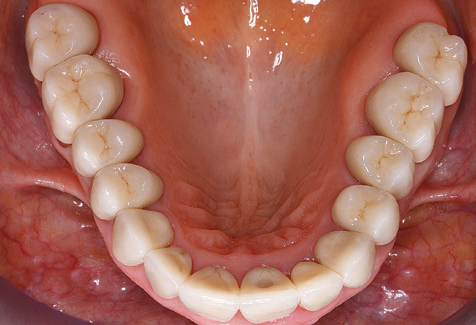

Standardised and regular risk-adapted care in the scope of SPT is the key to treatment success for the clinical long-term success in periodontically compromised patients. This is particularly true for patients fitted with implants following successfully completed periodontal treatment (Fig. 11a and b).